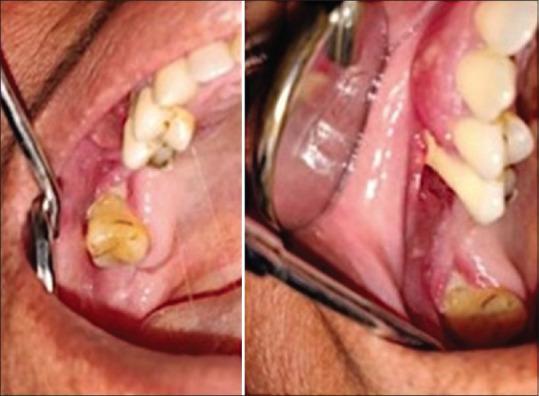

成人起病的朗格汉斯细胞组织细胞增多症——口腔中的“特洛伊木马”:一例罕见临床表现的病例报告

Adult-onset Langerhans cell histiocytosis - A Trojan horse of oral cavity: A case report with rare clinical presentation.

Department of Oral Medicine and Radiology, JSS Dental College and Hospital, JSS Academy of Higher Education and Research (JSSAHE&R), Mysuru, Karnataka, India.

Langerhans cell histiocytosis (LCH), earlier recognised as histiocytosis X, is a rare haematological illness involving infants and young children. LCH is caused by unrestrained stimulation and proliferation of usual antigen presenting cells, Langerhans cells (LCs) and the disease demonstrates extensive clinical and radiographic features involving multiple sites. Since the incidence is relatively low limited data is available regarding the epidemiology of LCH, with approximation of 2-5 cases per million populations per year. LCH has male predilection with jaws involved in 10-20% cases and only 1% of the cases affecting maxilla, masquerading as periodontal or periapical pathology. We report a case of 48-year-old female with LCH involving posterior maxilla. This is a unique presentation corresponding to age, gender, location and severity. Dental clinicians should be aware of this and consider it to be a part of their differential diagnosis pertaining to unresolved periodontal pathology as it mimics clinically and radiographically.

朗格汉斯细胞组织细胞增多症(LCH),早期被称为组织细胞增多症X,是一种罕见的血液疾病,主要累及婴幼儿。LCH是由通常的抗原呈递细胞——朗格汉斯细胞(LCs)不受控制的刺激和增殖引起的,该疾病表现出涉及多个部位的广泛临床和影像学特征。由于发病率相对较低,关于LCH流行病学的可用数据有限,每年每百万人口中约有2 - 5例。LCH男性多见,10% - 20%的病例累及颌骨,仅占上颌骨病例的1%,常表现为牙周或根尖周病变。我们报告一例48岁女性LCH累及上颌后部的病例。这是一个在年龄、性别、部位和严重程度方面都很独特的表现。牙科临床医生应意识到这一点,并将其视为与未解决的牙周病变相关的鉴别诊断的一部分,因为它在临床和影像学上都有相似表现。